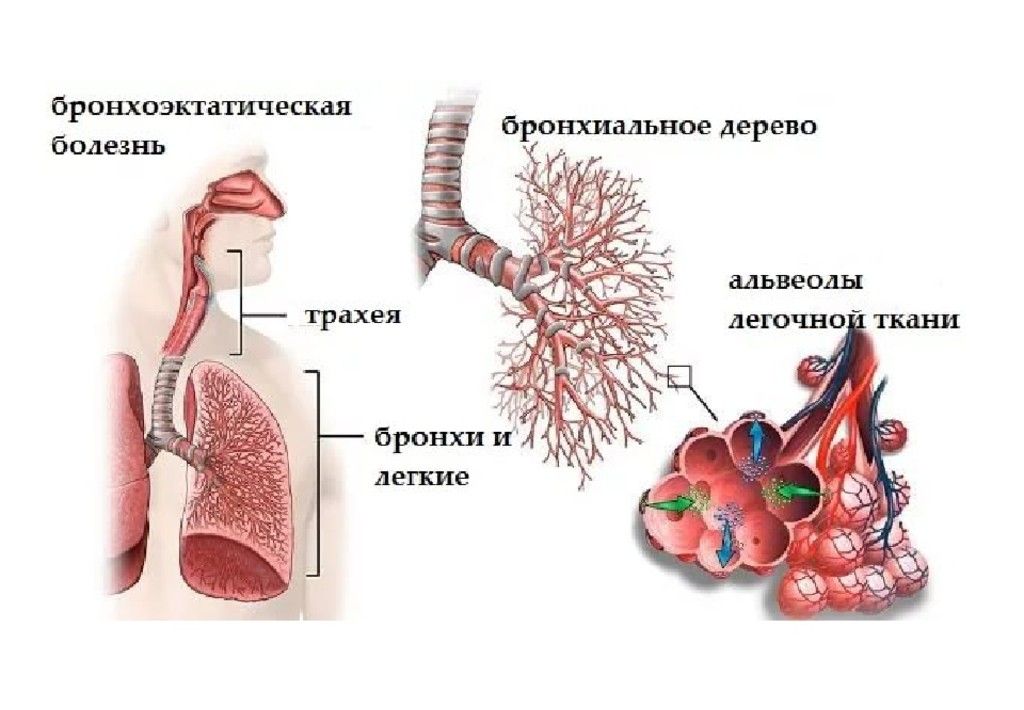

Фотографии заболеваний бронхолегочной системы